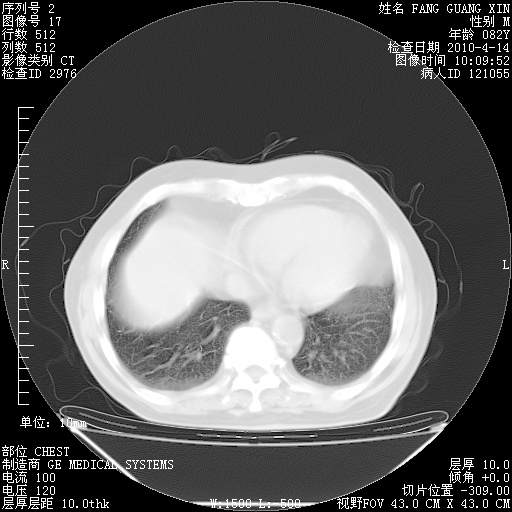

4月14日肺部CT

肺部CT平扫未见异常。